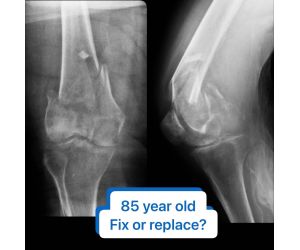

What if Quadriceps Alignment was variable?

Dr. Simon Talbot

Welcome to the very first video in my series on Quadriceps Alignment. These will be very short videos, but it looks like there might be quite a lot...